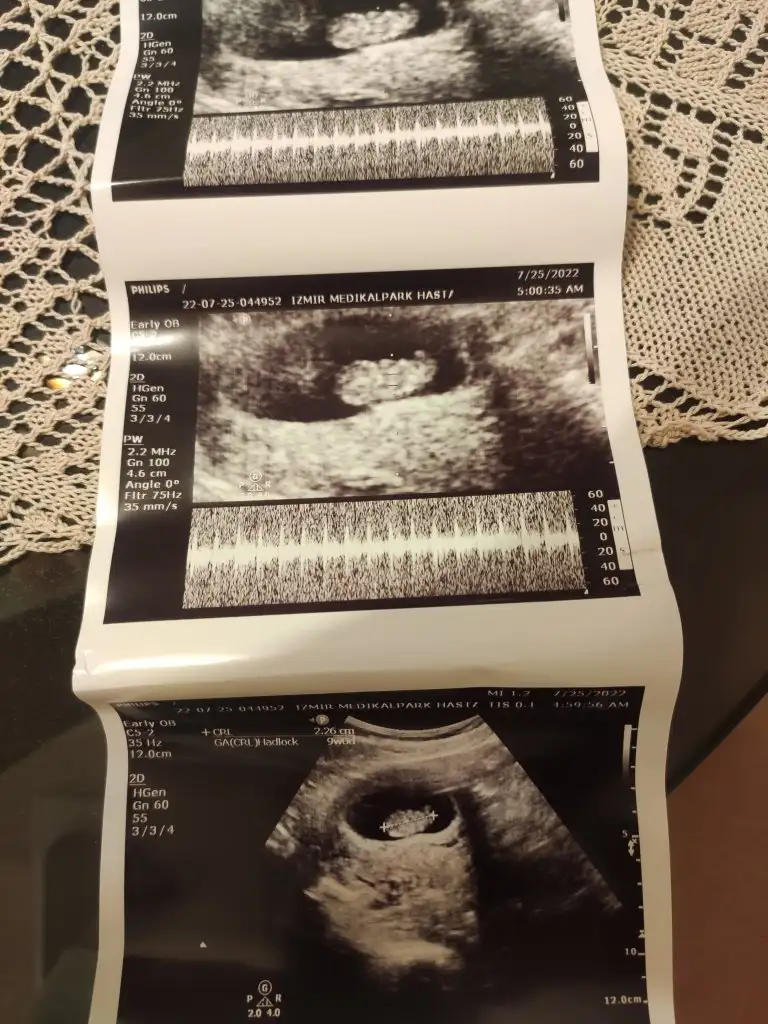

Bu isten daha çok anlayan hamisler bi baksin canimBilmiyorum sanki oda 20 değilde 2.0 cm gibi anlamadım

Evet bilen birileri varsa yazsınBu isten daha çok anlayan hamisler bi baksin canim![]()

Evet bende yok böyle birşey bilemedim neden acabaEki Görüntüle 3103237 @Azelya21 benimki böyle kuzum altta da bebişin boyutu yazıyor ama sende göremedim bunu

Bak benim en altta crl 2.26 cm yazan boyu altında da 9 hafta yaziyorEvet bende yok böyle birşey bilemedim neden acaba![]()

Anlaıdm benimkinde yazmıyor demekki olabilirBak benim en altta crl 2.26 cm yazan boyu altında da 9 hafta yaziyor